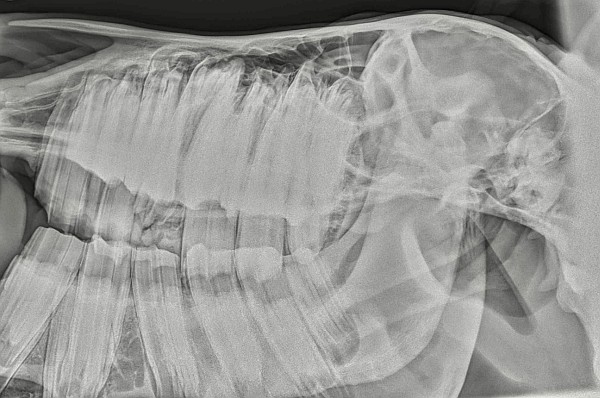

Modernes hochwertiges Equipment wie elektrische und manuelle Zahnraspeln, Zangen, Spreizer, Werkzeug zur minimalinvasiven transbuccalen Zahnextraktion, Zahnendoskop, sowie mobile digitale Röntgentechnik ist selbstverständlich und ermöglichen eine fachgerechte Behandlung des jeweiligen Zahnproblems nach neuestem wissenschaftlichen Standard.

Am sedierten Patienten besteht dann die Möglichkeit, einer vollständigen Untersuchung der Maulhöhle. Nach Anlegen eines Maulgatters kann die gesamte Maulhöhle abgetastet werden. Außerdem wird, nach Ausspülen von Futterresten, die gesamte Maulhöhle optisch untersucht. Hierzu wird eine endoskopische Kamera mit externem Bildschirm verwendet, sodass auch dem Patientenbesitzer die Zahnbefunde des Pferdes optisch dargestellt werden können. Bei weitergehenden Untersuchungen können vor Ort auch andere bildgebende Verfahren wie Röntgen zum Einsatz kommen.

Die Methode der zweiten Wahl ist die minimal invasive transbuccale Chirugie (Extraktion).Hierbei wird in die Wange (Backe) ein kleines Loch angebracht, durch welches ein metallener Arbeitskanal eingeführt wird. Durch diese Hülse erfolgen nun die weiteren Operationsschritte. Der Zahn kann nun mit Meißeln gelockert werden. Danach wird in den Zahn ein Loch gebohrt, in welches nun mit einem Gewindeschneider ein Gewinde gefräst wird. In das Gewinde wird eine Gewindestange geschraubt, an welcher der Zahn nun herausgezogen werden kann. Zur Überprüfung des Zahnwurzelverlaufs und der Bohrrichtung sind mehrere Röntgenaufnahmen nötig.

Die Methode der dritten Wahl ist die minimalinvasive Trepanation und Repulsion (früher als Steinmann Pin Methode bezeichnet), bei der von außen am Schädel ein 6 bis 8 mm großes Loch in den Knochen über dem zu ziehenden Zahn gebohrt wird, in den ein Stahl-Pin eingeführt wird, der unter strenger Röntgenkontrolle genau über dem Zahn positioniert wird. Dann wird der Zahn mit Hammerschlägen herausgetrieben. Dies geschieht unter Kontrolle von der Maulhöhle her und mit Hilfe von Röntgenaufnahmen. Falls möglich, werden die entstehenden Zahnlücken mit einer Zahnabdruckmasse aus der Humanmedizin verschlossen. Dieses Implantat wird dann in immer länger werdenden Zeitabständen mehrfach gewechselt.